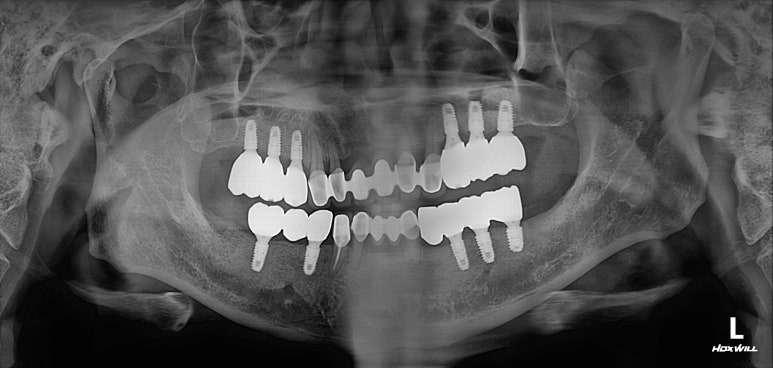

모든 최종 보철물을 연결하고 나서 치과용 파노라마 사진입니다.

정말 깔끔하게 제작된 것을 보시 수 있을겁니다.

'미적 기준'은 보편적인 측면이 있습니다. 뭔가 나란하고 비율이 대칭인 임플란트는, 잘 모르는 사람이 봐도 잘 되었구나~~ 라고 생각하게 만들어주죠 ^^

제가 가진 수술 경험을 비롯한 노하우와, 오스템 임플란트의 네비게이션 임플란트 시스템이 합작해낸 결과물!

양쪽 위 어금니 부위에 깔끔하게 3개씩 임플란트를 심어드렸습니다.

이 3개의 임플란트는 시간이 흘러 첫번째, 두번째 작은 어금니 그리고 첫번째 큰 어금니가 됩니다.

치과용 파노라마 사진 상에서 잘 확인하기 어려우실 수 있지만,

화살표로 표시해둔 곳까지 측방접근법 상악동 뼈이식술이 성공적으로 잘 된 것을 확인할 수 있습니다.

개수가 조금 더 적어보이는 것은, 아래턱 뼈가 위턱뼈보다 더 딱딱하기 때문입니다.

비교적 적은 임플란트로도 성인 남성의 씹는 힘을 견딜 수 있거든요!!!

한편으로 상악동 뼈이식술까지 필요했던 케이스이니... 더더욱이 위턱뼈엔 임플란트가 많이 필요했던 상황이었죠.